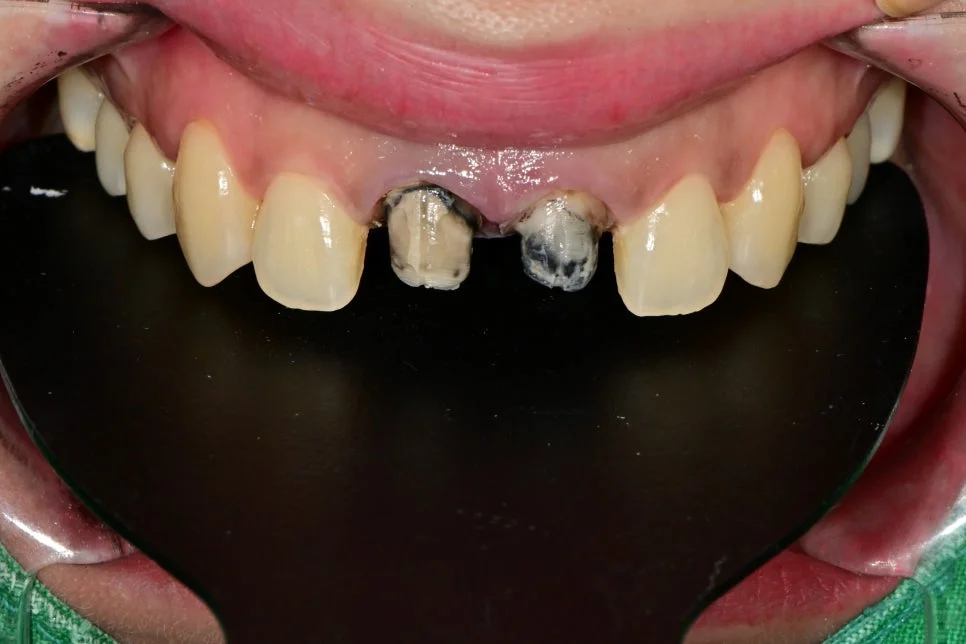

크라운 제거 후 모습입니다.

제거하기 전 예상보다 훨씬 더 크라운 잇몸 변색이 심한 상태였는데요. 이렇기에 조기에 치료하는 게 매우 중요합니다.

안쪽을 확인해봐도 오염이 심하게 진행된 상태가 보여집니다.